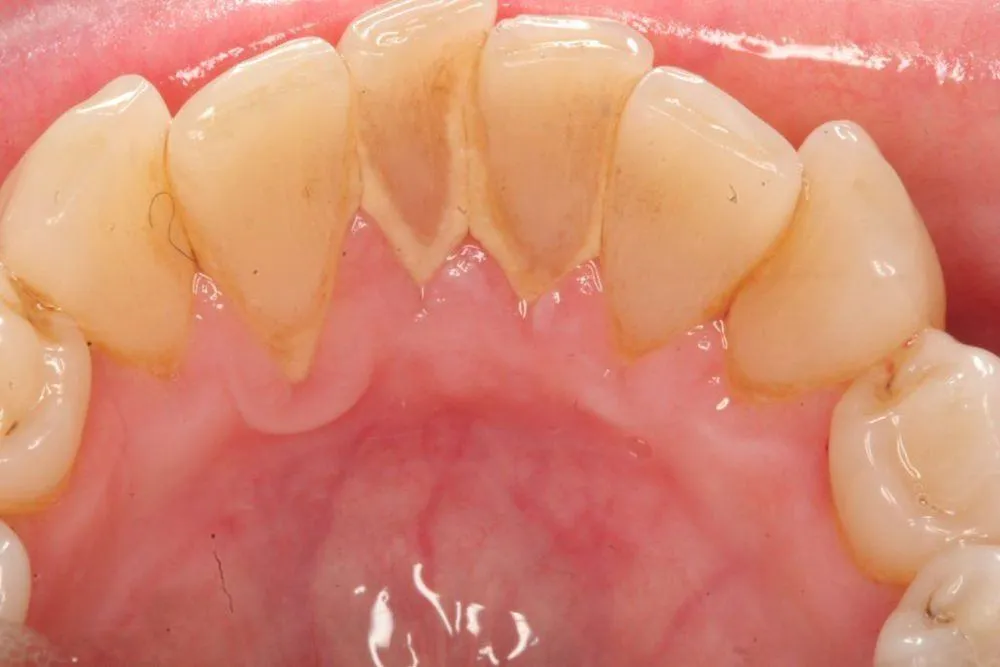

Trước khi tìm hiểu các cách làm rụng cao răng tại nhà thì cần biết cao răng là gì. Cao răng là những mảng bám, màu vàng hoặc nâu, dính chặt vào bề mặt răng. Đây là kết quả của quá trình vi khuẩn hoạt động mạnh. Những vi khuẩn này nằm trên các mảnh vụn thức ăn dư thừa bám lại trên răng. Thông qua đó chúng sẽ tạo thành mảng bám mềm. Sau một thời gian, mảng bám này dần chuyển hóa thành cao răng. Điều này do khoáng chất trong nước bọt kết hợp với vi khuẩn và chất thải sinh học.

Cao răng không chỉ làm mất đi vẻ đẹp thẩm mỹ của nụ cười. Nó còn là tác nhân gây ra nhiều vấn đề sức khỏe nghiêm trọng cho răng miệng. Nếu không được loại bỏ kịp thời, cao răng có thể dẫn đến các bệnh lý. Ví dụ như sâu răng, viêm nướu và viêm nha chu. Từ đó ảnh hưởng đến sức khỏe tổng thể của răng miệng. Khi cao răng bám lâu ngày, chúng sẽ tạo thành môi trường lý tưởng cho vi khuẩn phát triển. Điều này dẫn đến tình trạng viêm nhiễm và có thể làm tiêu xương hàm.